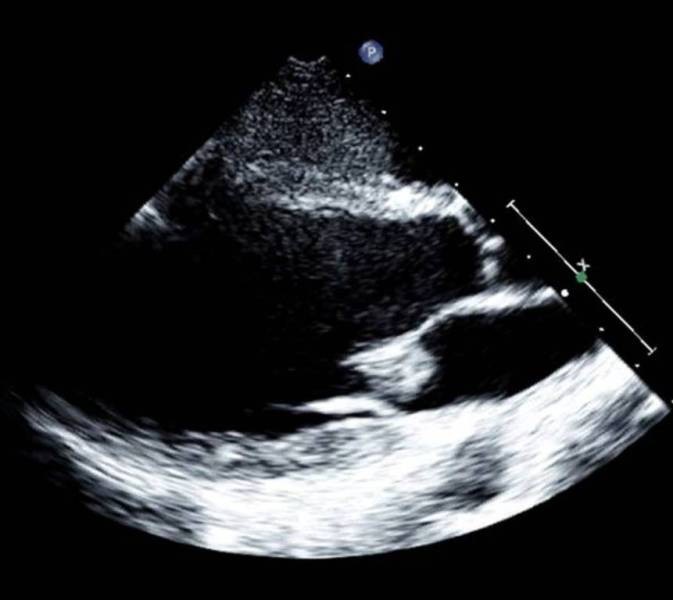

Figure 2From: Complication of nasal piercing by Staphylococcus aureus endocarditis: a case report and a review of literatureTransthoracic echocardiogram showing a mitral vegetation of 15 × 13 mm on the anterior cusp.Back to article page